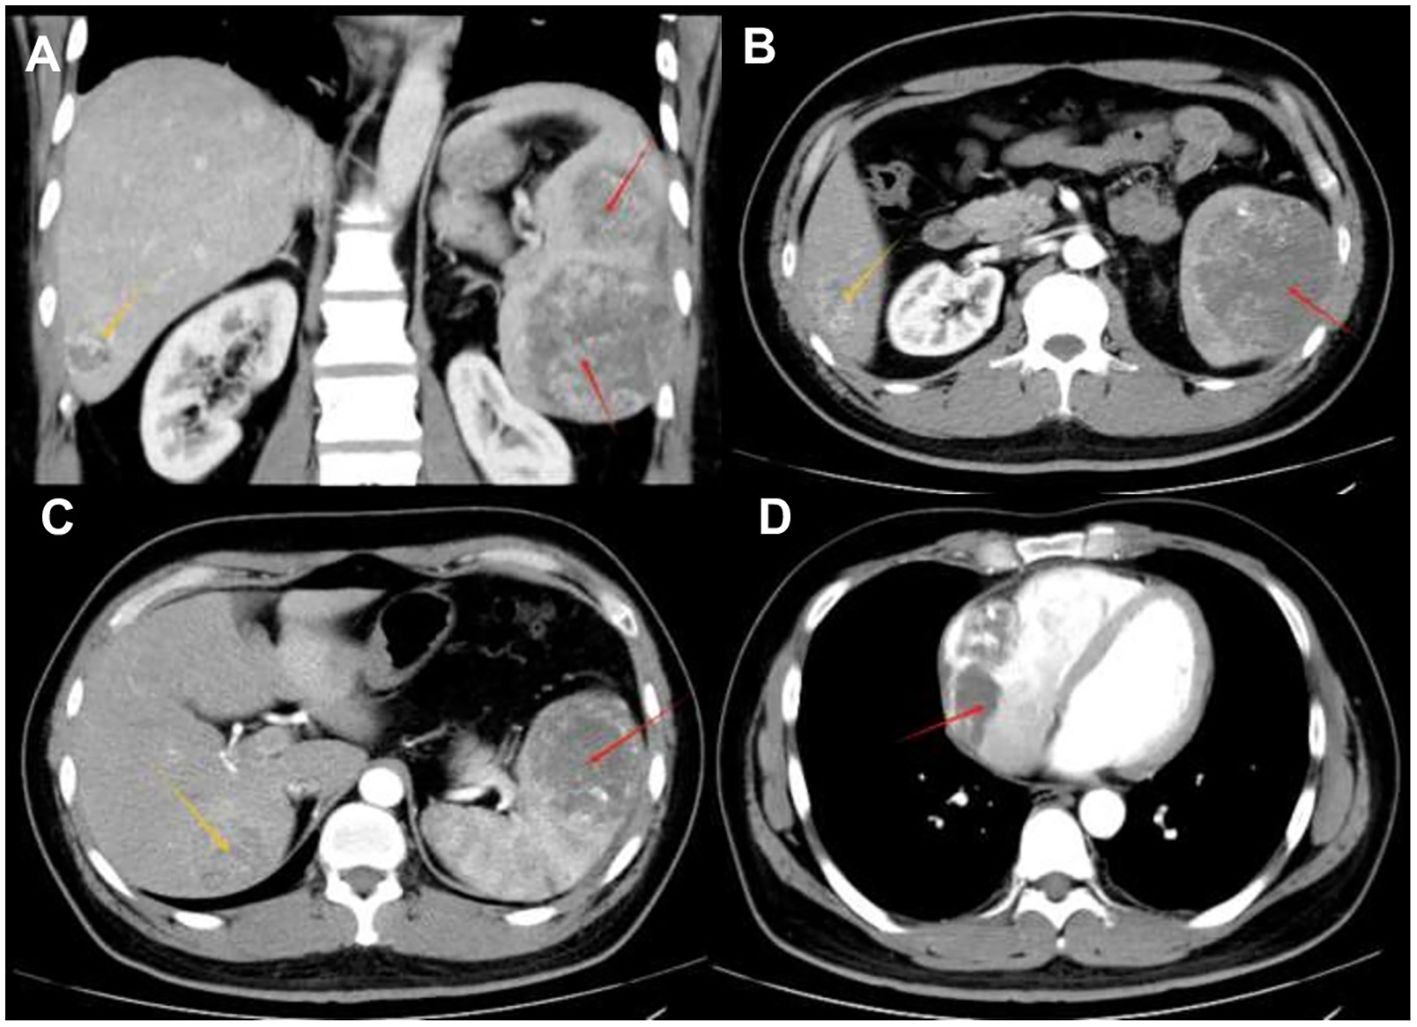

The patient is a 35-year-old male who was admitted to the hospital due to intermittent severe pain in the left abdomen for more than two months. Regarding the tumor, vascular computed tomography angiography (CTA) (Figure 1) revealed multiple circular mixed-density lesions in the spleen and the splenic tumor was compressing the left kidney. The tumor in the inferior pole protrudes locally outside the spleen contour, with a size of approximately 6.3 cm×7.3 cm×13.6 cm. Besides, CTA showed multiple circumscribed lesions with circular and heterogeneous enhancement in the liver. The larger one was located in segment VII of the liver, with a size of approximately 4.1 cm×4.0 cm×3.5 cm. CTA showed an inhomogeneous enhancement tumor in the right atrial region, with a maximum diameter of 7.1 cm. Due to the presence of surface ulcers and perisplenic hemorrhage in the patient’s splenic tumor, there is an extremely high risk of life-threatening spontaneous rupture. Additionally, the patient has asymptomatic cardiac metastasis without acute heart failure or hemodynamic instability. We performed laparoscopic partial hepatectomy and laparoscopic splenectomy on the patient.

Figure 1. Radiological findings (A) A tumor within the spleen can be seen compressing the left kidney in the coronal position. (B) Contrast-enhanced CT shows multiple circular mixed-density lesions in the spleen. The size of the lesion in the inferior pole of splenic area is approximately 7.3 cm×6.3 cm×13.6 cm (indicated by the red arrow). Unevenly enhanced lesions can be seen in the V segment of the liver, approximately 3.7 cm×4.1 cm×4.5 cm in size (indicated by the yellow arrow) —consistent with typical SA liver metastasis. (C) An unevenly enhanced lesion with a size of approximately 4.1 cm×4.0 cm×3.5 cm (indicated by the yellow arrow) can be seen in segment VII of the liver. The lesion in the superior pole of the spleen is approximately 7.3cm×6.8cm×7.0cm in size (indicated by the red arrow). (D) Contrast-enhanced CT shows an unevenly enhanced lesion in the right atrium, with a maximum diameter of 7.1 cm (as indicated by the red arrow) —a rare metastatic site in SA, reported in only 1% of cases.